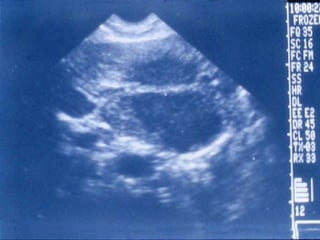

SONOGRAMA ABDOMINAL EVALUACIÓN  MASA QUISTICA EN HIGADO Masa con ausencia de ecogenicidad en su interior Paredes lisas y nítidamente definidas Refuerzo acústico más allá de la pared posterior